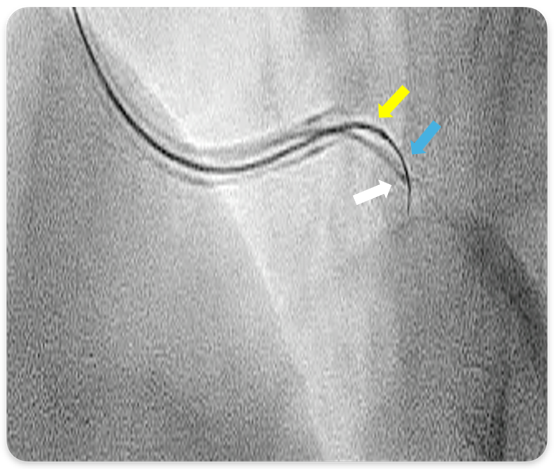

Coronary angiography revealed subtotal occlusion at the ostium of the left anterior descending artery (LAD) (Figure 1). Percutaneous coronary intervention (PCI) was initiated, aiming at minimal contrast use. Using a 7F Extra Back-Up guiding catheter (Medtronic), the left circumflex artery (LCx) was first wired for protection. A SASUKE dual-lumen microcatheter (ASAHI INTECC) was inserted into the LCx, and an attempt was made to wire the LAD using a polymer-jacketed FIELDER FC wire (ASAHI INTECC) through the dual-lumen microcatheter. However, wiring the ostial LAD lesion proved challenging without contrast injection. There was no obvious landmark (eg, calcium) at the ostial LAD, and the wire easily got into 2 small branches that were present near the ostium (Figure 1), the course of which was easily mistaken as the LAD. It was essential to confirm that the wire was in the LAD before stepping up to a penetrating wire.